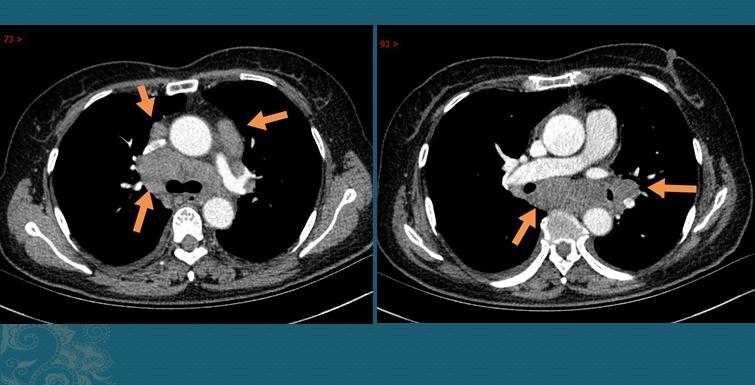

2.一位40多岁的女士,偶尔胸闷、咳嗽,也做了一个CT,发现纵隔多发肿大淋巴结:

我们知道,淋巴结肿大常见于癌细胞转移,很多小细胞肺癌和低分化腺癌病人,肿瘤发展快,可以在较短的时间内发生纵隔多发淋巴结转移,有些病人在出现症状时就已经是晚期……

1.肺门周围及纵隔多发肿大淋巴结。

这种类型最常见(约占77%),如上图第二位女病人,有时需要与淋巴结结核、恶性肿瘤鉴别;

1.胸部CT发现对肺门及纵隔淋巴结对称性肿大(增强CT呈均匀强化),伴或不伴肺内多发网格状、斑片状、结节状影;